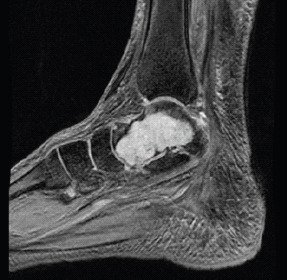

Figure 3.

T1-weighted sagittal section of ankle showing lobulated hypointensities in the talus.

Figure 4.

T2-weighted sagittal section of ankle showing heterogeneously hyperintense lesion in the talus.